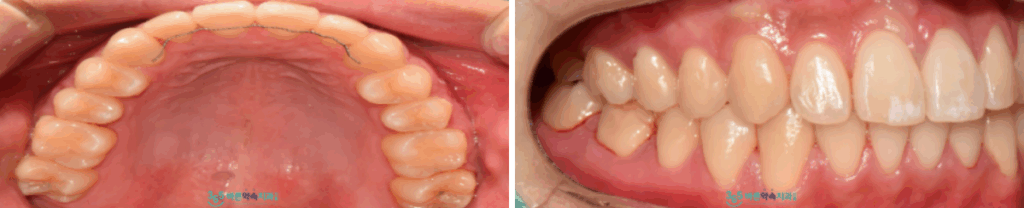

비발치 교정치료가

마무리된 구강 내 사진인데요.

안으로 들어가 있던 송곳니가

제 위치로 돌아오고

안정적인 교합을 되찾은 모습입니다.

환자분께서는 입을 벌렸을 때

턱관절에 불편감이 사라지고

웃는 모습에 자신감이 생겨

만족해하셨습니다.